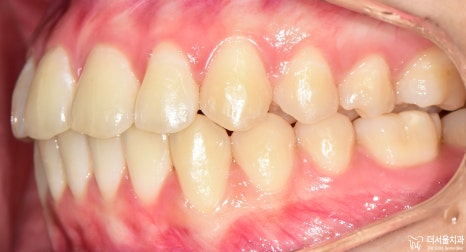

측면에서는 확연히, 돌출입 형태를 확인하실 수 있습니다. 이렇게 앞니들이 앞으로 뻐드러져

있는데 심미선을 기준 으로 봤을 때 입술의 위치가 그대로 예쁜 곳에 있는 걸 보면

연조직이 얇아서 가능하다라는 것을 추측할 수 있겠네요.

아울러, 이 분의 경우에는 비발치 교정 으로 치료를 하길 원하셨었습니다.